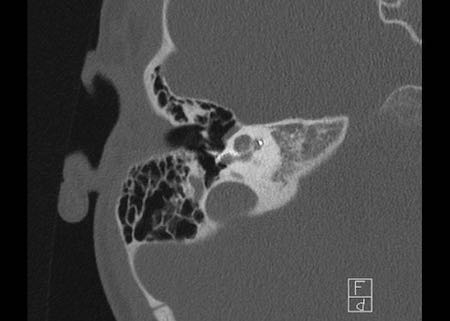

Bên trái là hình ảnh của một bé gái 2 tuổi.

Các hình ảnh từ kết quả chụp CT được thực hiện trước khi cấy ốc tai điện tử.

Quan sát thấy dị dạng nhẹ ở đỉnh ốc tai – không có sự phân tách giữa vòng thứ hai và vòng thứ ba, và trụ ốc tai xương vắng mặt.

Cống tiền đình bình thường.